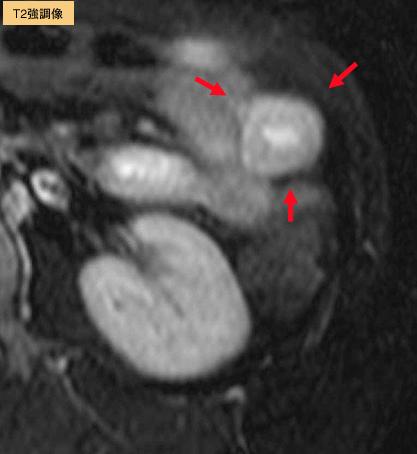

질환(병리주체)의 분류 악성 비상피성종양/평활근육종

부위(장기별) 소장/공장

검사방법 MRI

종양의 최대경(밀리미터) 30~34

종양의 심달도 s(a)